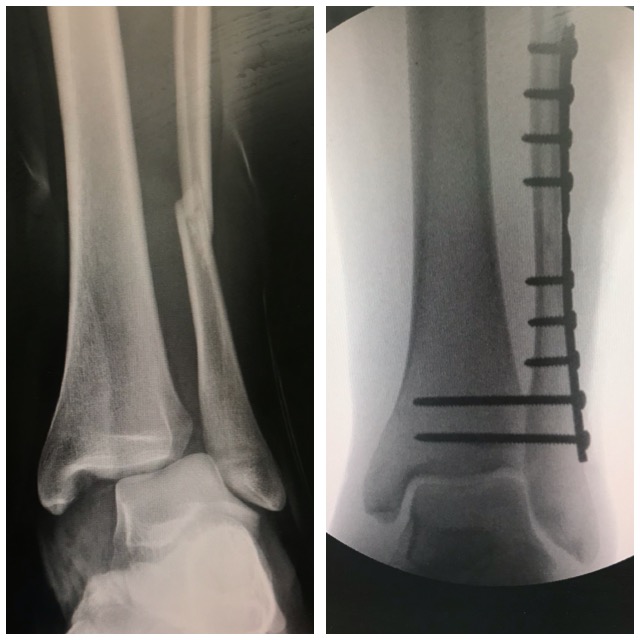

Säärimurtuma

Ennen – jälkeen